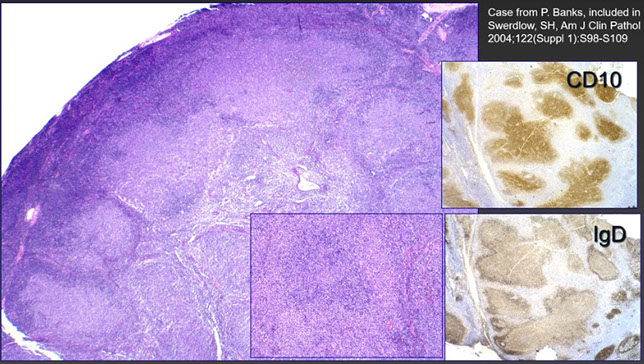

Nodular lymphocyte predominant Hodgkin lymphoma (NLPHL)